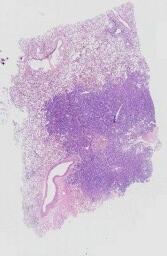

临床资料: 患者女性,71岁,发现甲状腺结节10+天。患者无意间发现甲状腺结节,结节无痛,初期无呼吸困难,表面皮肤无红肿,无食欲亢进、消瘦、手抖、饮水呛咳等不适,无怕热多汗及性情改变,无发热、寒战、心慌不适。患者至武胜县中医院就诊,甲状腺彩超提示甲状腺左叶4c类结节,大小约22*27*33mm,左颈IV见淋巴结增大,结构显示不清。

大体所见: 灰白结节一个,大小4cm×3cm×3cm,表面附着少许甲状腺,切面灰白、实性、质中偏韧,见坏死。